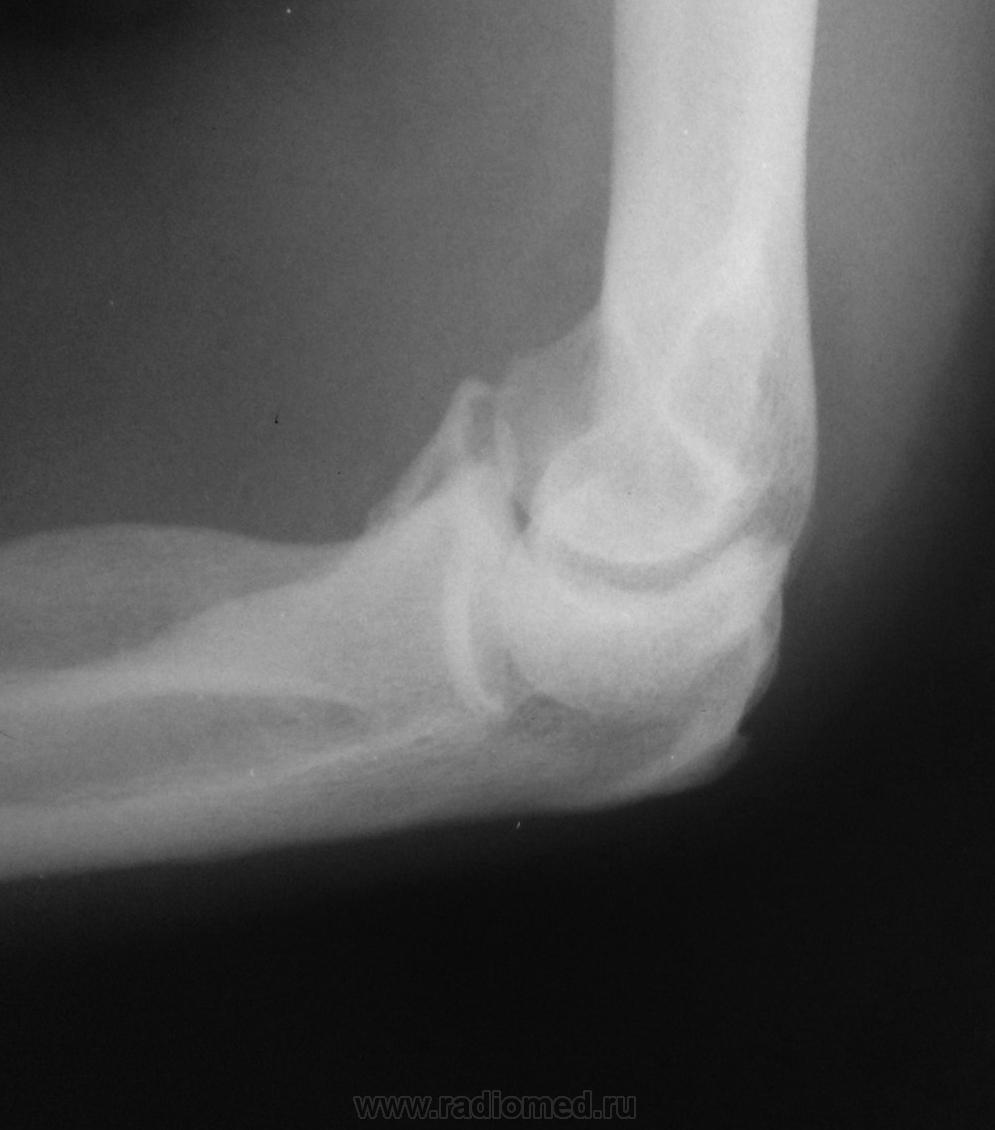

Есть ли перелом венечного отростка?

Возник вопрос. Посмотрите , пожалуйста.

Под большим сомнением. А укладка нарочно нестандартная?

На мой взгляд есть, есть без сомнений.

Сделайте внушение рентгенолаборанту за такой боковой снимок.

Сначала подумал, что страдает укладка (а она страдает), "грешил" на суставные поверхности, перелом под сомнением. Но всё же, судя по клинике, выставил перелом венечного отростка.

Написал бы костно-травмат. изменений не выявлено. Переснять в строго боковой проекции ...

Нет, уважаемый коллега, НЕТ!

Не по клинике, а по скиалогии!

Последний снимок - "норма" для сравнения.

Чем объясним неровность и нечёткость контура, помеченные красными стрелочками?

О чем мы гадаем? Тем более в фантатических (типа локального остеосклероза) терминах. Снимите в боковой (не в как бы боковой, а в строго боковой) проекции - будет тема для разговора.